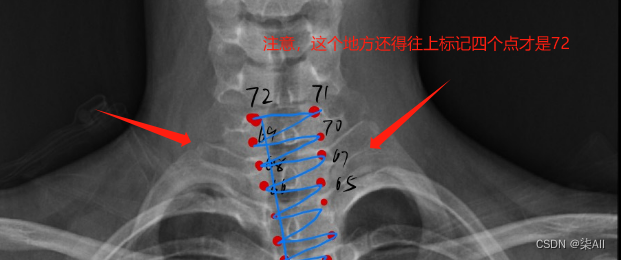

冠状位(一共是标记72个关键点)

左右bending(一共也是标记72个关键点)

左bending和右bending是一样的,这里就做一个示范

(1)标注的椎体应该近似是一个矩形,而不是梯形 如下图

(2)标注的时候关键点 不要(X)标记的太靠 边 ,但是 也不要往内收的太厉害